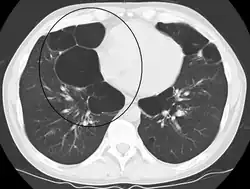

A chest X-ray and complete blood count may be useful to exclude other conditions at the time of diagnosis.[82] Characteristic signs on X-ray are hyperinflated lungs, a flattened diaphragm, increased retrosternal airspace, and bullae, while it can help exclude other lung diseases, such as pneumonia, pulmonary edema, or a pneumothorax.[83] A high-resolution CT scan of the chest may show the distribution of emphysema throughout the lungs and can also be useful to exclude other lung diseases.[25] Unless surgery is planned, however, this rarely affects management.[25] A saber-sheath trachea deformity may also be present.[84] An analysis of arterial blood is used to determine the need for oxygen; this is recommended in those with an FEV1 less than 35% predicted, those with a peripheral oxygen saturation less than 92%, and those with symptoms of congestive heart failure.[24] In areas of the world where alpha-1 antitrypsin deficiency is common, people with COPD (particularly those below the age of 45 and with emphysema affecting the lower parts of the lungs) should be considered for testing.[24]